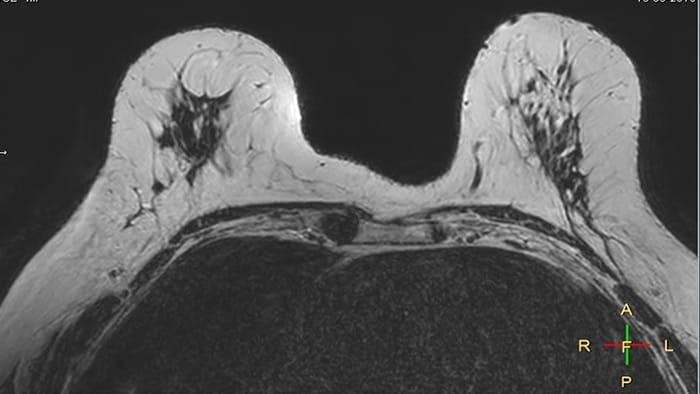

Compressed SENSE, scan time 3:54 min Voxels acq 0.8 x 0.72 x 1.8 mm Voxels recon 0.63 x 0.63 x 0.9 mm

C-SENSE factor 12

SENSE, scan time 6:32 min Voxels acq 0.8 x 0.8 x 1.8 mm Voxels recon 0.63 x 0.63 x 0.9 mm

SENSE factor 3

The time gain with Compressed SENSE was also used to increase resolution in order to help radiologists identify the tumor characteristics more confidently which may be used for a more personalized treatment. For example, in breast imaging, resolution is crucial for visualization of very small lesions. Compressed SENSE allows to scan thinner slices, allowing a 3D isotropic sequence which can provide increased diagnostic confidence for the radiologists.

“The 3D-THRIVE sequence has proven to be important in providing detailed post-processing data to inform on diagnosis and how we care for the patient,” says Ruth Pearson. “Normally, if you want more detail on an MRI scan, the scan takes longer. Previously we’ve had to balance between getting the detail required and how long the patient can lie still. Now with the Compressed SENSE technology, we can get more detail and scan faster.”